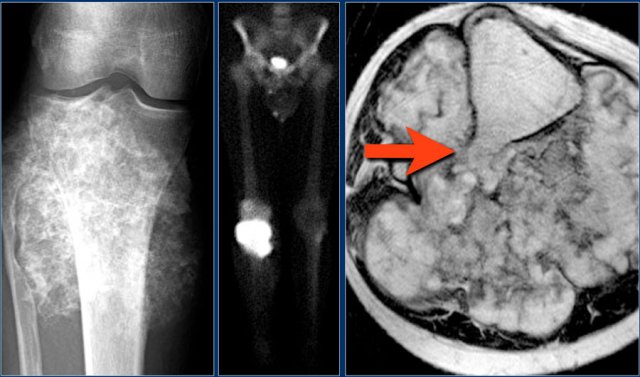

Here a NHL presenting as a non-specific ill-defined mixed osteolytic-sclerotic lesion in the proximal tibia.

Here a bone lesion in a patient with known NHL.

The imaging findings are non specific.

Here a subtle osteolytic metastasis in the distal femur.